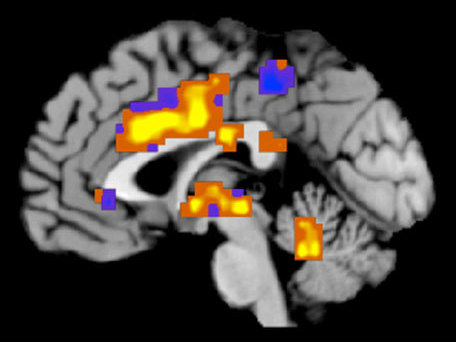

A technique for imaging the brain allowed researchers to distinguish between physical and emotional pain. (Courtesy of Tom Wager)